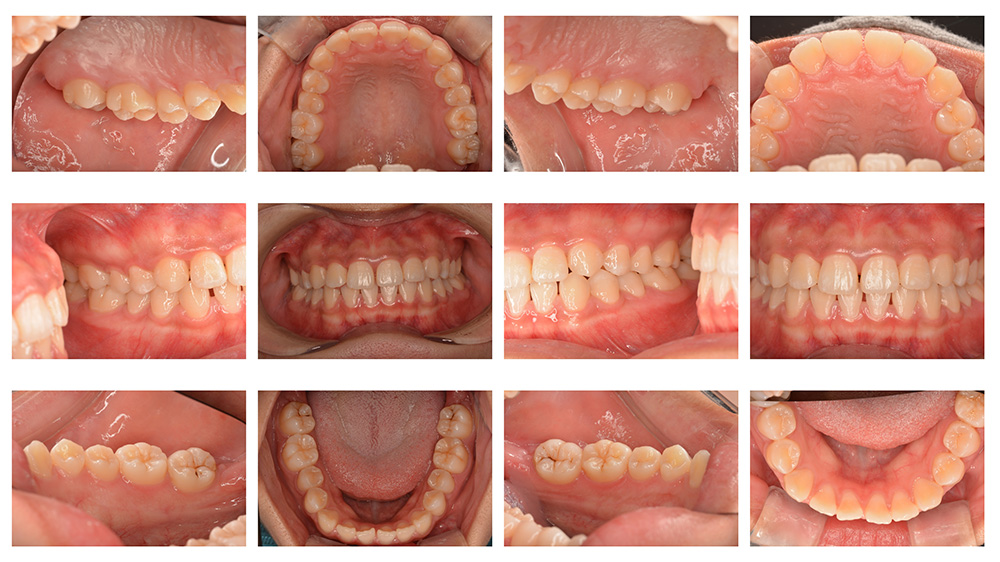

術前

術後

世代・性別

40代女性

主訴

歯を白くしたい

治療内容

オフィスホワイトニング+CAPシステム

治療期間

1ヶ月

治療費

50,000円(税別)

治療のリスク

知覚過敏症状